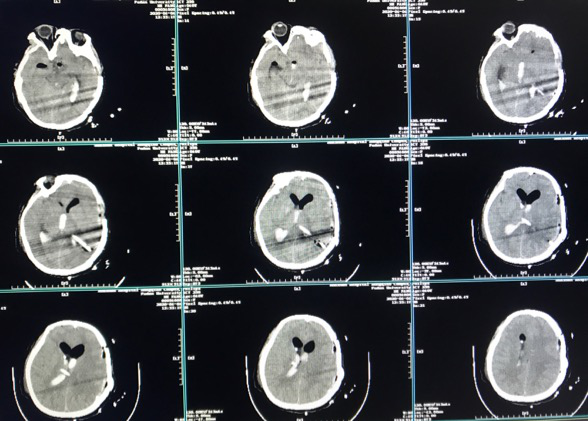

早查房时突发意识障碍。

备选方案:

脑室内血肿清除+动脉瘤切除+低流量搭桥。

术后CT

在本例病例中,针对脑室内动脉瘤,我们首选血管内治疗栓塞脑室旁动脉瘤,因为血管过于迂曲尝试失败。术后出现脑室内出血,于是启动备选方案,急诊在磁共振导航下通过endoport辅助进行动脉瘤切除,同时部分清除脑室内血肿并放置脑室外引流,降低远期脑脑积水的风险。随着神经内镜的普及,深部的脑血管病变的治疗方案有了更多的选择,而充分的术前评估与周全的手术方案规划是手术安全与成功的基石。